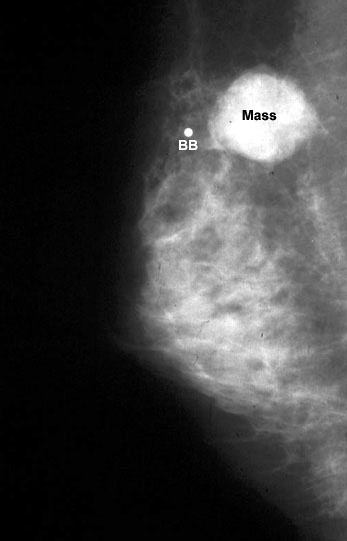

Mamografi (Altın Standart):

Mikrokalsifikasyonlar: LR (+) 15.0. (Özellikle pleomorfik/dallanan tipteyse)

Spiküle Kitle: LR (+) > 20.0.

"Mamografide Spiküle (Dikenli) Kitle Varlığı ile Luminal A Alt Tip Meme Kanseri Arasında Bir Korelasyon Var mıdır?"

Bu çalışma, mamografik görüntüleme bulguları ile meme kanserinin moleküler alt tipleri arasındaki biyolojik bağı incelemektedir. 317 hastanın retrospektif analizi üzerinden yapılan çalışma, fenotip (görüntü) ile genotip (moleküler belirteçler) arasındaki ilişkiyi Bayesyen bir olasılık çerçevesinde sunar.

1. Temel Bulgular ve İstatistiksel Veriler

Luminal A Dominansı: Spiküle (kenarları ışınsal uzantılı) kitlelerin %71'i Luminal A alt tipi olarak sınıflandırılmıştır.

Olasılık Oranı (Odds Ratio): Luminal A alt tipindeki kitlelerin, diğer alt tiplere oranla mamografide spiküle görünüm sergileme olasılığı 10.3 kat daha fazladır (p < 0.001).

Biyobelirteç Korelasyonu: Spiküle görünümün en güçlü öngörücüleri Düşük Ki67 indeksi (< %14) ve HER2 negatifliğidir. Hormon reseptör (ER/PR) pozitifliği de ilişkili bulunmuştur ancak etkisi Ki67 ve HER2 kadar baskın değildir.

İyi Prognoz İşareti: Spiküle marjlar, genellikle tümör hücrelerinin çevre dokuyla (stroma/yağ dokusu) etkileşimini ve düşük dereceli (low-grade) progresyonu gösterir. Bu durum, spiküle kitlelerin neden daha iyi bir prognoza işaret ettiğini açıklar.

Tanısal Doğrulama: Eğer bir tümör mamografide spiküle görünüyorsa ancak patolojide "HER2 pozitif" geliyorsa, bu bir uyumsuzluk (discordance) bayrağıdır; testin tekrarı düşünülebilir.

3. Sonuç

Mamografide görülen spiküle kitle, invaziv meme kanserinin Luminal A alt tipi için güçlü bir radyolojik belirteçtir. Bu korelasyonun temelinde tümörün düşük proliferatif aktivitesi (Ki67) ve HER2 gen ekspresyonunun olmaması yatar. Bu veriler, "spiküle kitle" verisinin, biyopsi öncesi Luminal A olasılığını (prior probability) belirgin şekilde yükselttiğini kanıtlamaktadır.